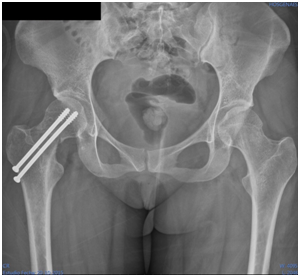

After study protocol patient was treated with surgical reduction and internal fixation with two cannulated screws, recovering diaphyseal cervical angle at 130º (Figure 4), and starts with partial discharge after two weeks of the surgery. Bone callus formation is identified two months after surgery (Figure 5), initiating total support of the limb 3months after surgery, and at 6months he fully reincorporates her activities with excellent clinical evolution. After two years of follow-up on his control radiographs, no avascular necrosis of the femoral head was observed and adequate bone remodeling appreciated (Figure 6).

Figure 4 20/10/2015 pelvic anteroposterior radiograph after surgical reduction and internal fixation with two cannulated screws.